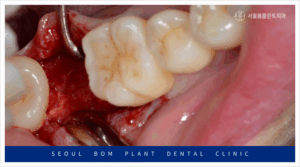

발치 후 3개월이 지난 뒤,

임플란트 식립을 위해 잇몸을 절개하고

골 내부 상태를 확인한 결과,

발치 당시 심한 염증이 있었던 부위가

잇몸뼈 회복이 더디게 이루어져

움푹 패인 상태를 보였습니다.

이렇게 잇몸뼈가 부족한 상태에서

무리하게 임플란트 식립을 하게 되면,

식립한 임플란트가 고정력을 얻지 못하게 되어,

결국 흔들리거나 금세 탈락하는 등의

문제가 발생할 수 있습니다.

이로 인해 임플란트의 장기적인

안정성을 확보하기 어려워지며,

임플란트의 기능을 제대로 발휘할 수 없습니다.

따라서, 임플란트를 오랫동안 건강하게

사용하기 위해서는 뼈이식이 필요한 경우가 많습니다.